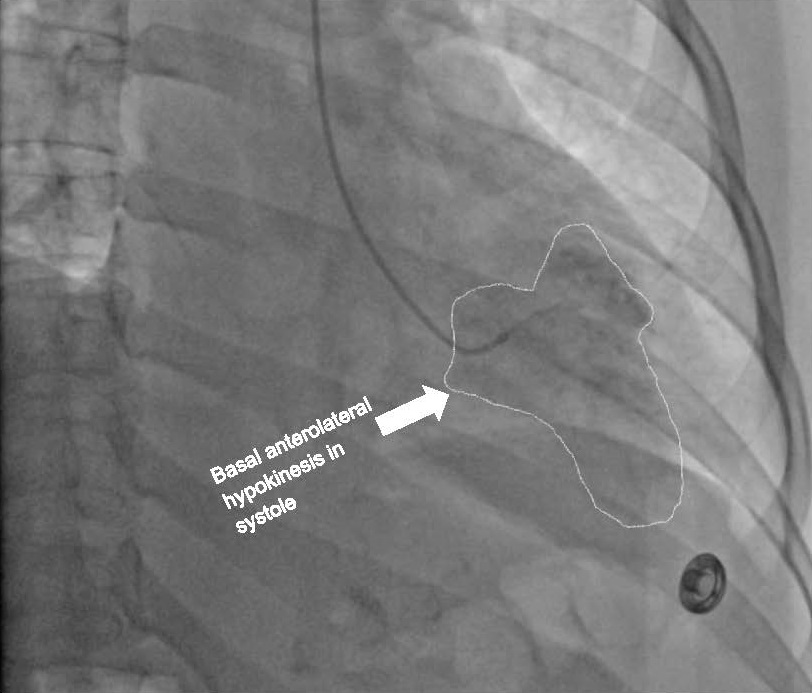

New case report! "A Rare Case of Iatrogenic Inverted Stress Cardiomyopathy” by Drs. Parviz-Ali Lotfian, Arun Umesh Mahtani, Seyed Zaidi, & Richard Grodman RUMC in Staten Island. #cardiotwitter #MedEd #DeBakeyCVJournal doi.org/10.14797/mdcvj…

New case report! "A Rare Case of Iatrogenic Inverted Stress Cardiomyopathy” by Drs. Parviz-Ali Lotfian, Arun Umesh Mahtani, Seyed Zaidi, &amp; Richard Grodman <a href="/RUMCSI/">RUMC</a> in Staten Island. #cardiotwitter #MedEd

#DeBakeyCVJournal doi.org/10.14797/mdcvj…